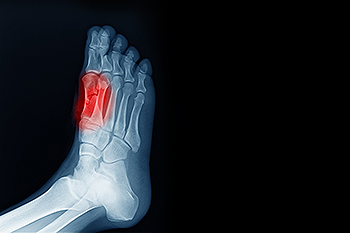

The sesamoids are two tiny, pea-shaped bones located just beneath the big toe. These free-standing bones allow the big toe to move normally. They also provide leverage when you push off the big toe while walking or running. The sesamoids can be fractured during physical activities like running, hiking, or playing sports. Broken sesamoid bones cause deep, aching, or sharp pain in the ball of the foot behind the big toe. The surrounding area may be red or swollen. Sesamoid fractures are generally diagnosed through X-rays. Treatment may include wearing flat, rigid shoes specially designed to hold bones in place while they heal. Wearing orthotics and certain medications can help to manage pain. If you are having pain in your foot, it is suggested you make an appointment with a podiatrist for care and treatment options.